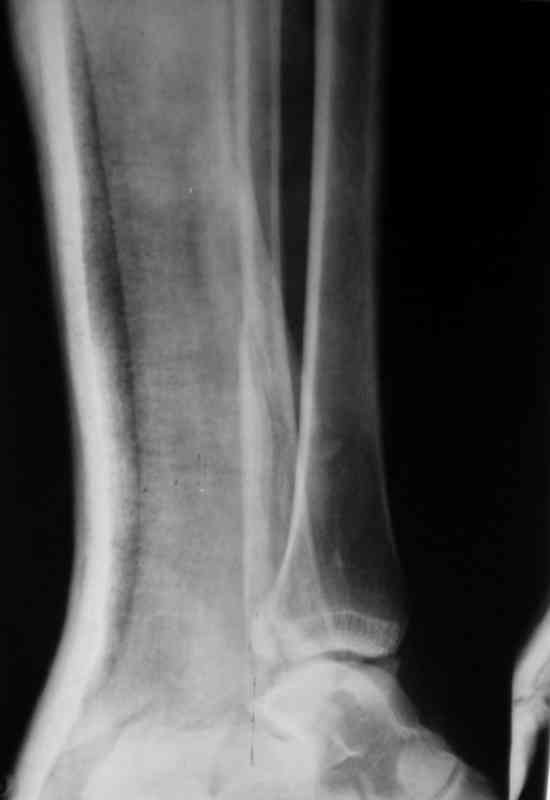

Вот рентгенконтроль на 7-е сутки после репозиции.

Серега, привет! А что наш ув.доцент А.П.М. говорит по этому поводу. И вообще, я не знал, что ты лечишь 3-хлодыжечные задними лонгетами, - нас с тобой учили это делать циркулярными гипсовыми повязками. Все равно, удачи! На контроле, почему-то, все заманчиво хорошо. Не спеши делать выводы

Стандартными снимками считается прямая, боковая и мортиз!!!, а так трудно гадать, насколько потеря длины малоберцовой. На боковом снимке не сопоставленный перелом медиальной лодыжки и перелом заднего края без смещения.

Трехлодыжечные переломы относятся к нестабильным переломам, при вовлечении перелома заднего края больше 15% суставной поверхности и смещения более 2 мм тогда такие переломы необходимо оперировать.

Трудно удержать трехлодыжечные переломы задней лонгетной повязкой (на снимке), а последующие долгие гипсовые повязки могут привести к контрактурам.